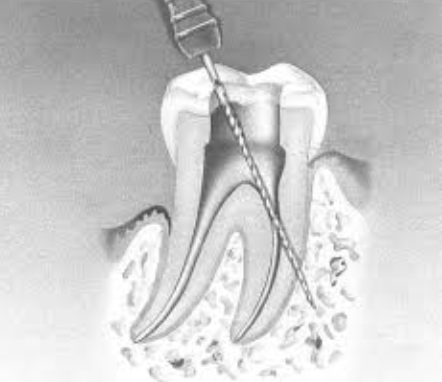

Perforations Radiculaires : Prévention, Détection et Réparation

Perforations radiculaires article · MD Copier Perforation...

Perforations radiculaires article · MD Copier Perforation...